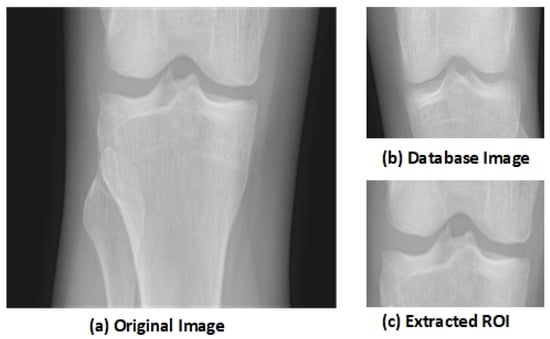

The key aspect of the algorithm is detecting the early KOA disease space width of the knee joint. This disease becomes advanced as the gap between knee joints increases with age. The region of interest (ROI) is the tibiofemoral joint. The ROI is calculated through a matching technique with the database of knee images. The database image moves on the input image pixel by pixel, and the similarity among the image’s blocks through a histogram of gradients’ features is computed. The block, having maximum similarity, is selected as the ROI. This similarity-based mechanism outperforms the traditional algorithms. Let us suppose that an input image I of knee is fed to the system having size I × J, and D represents the database image, having size × , where is the vector of HOG, having a size of 1 × h of the database image D. and is the block of d × that is located at (m,n) in the image I. The HOG feature of is represented as . Mean absolute difference (MAD) is used to compute the similarity among the database image D and the image block

The block with the minimum MAD is selected as the ROI that contains the knee joint. The knee image that is used in the database is shown in Figure 1b. Figure 1a shows the original knee image, while Figure 1c shows the selected ROI. The selected region has essential features as it shows the joint space width (JSW).

Figure 1.

Extraction of Region of Interest (ROI) [48].